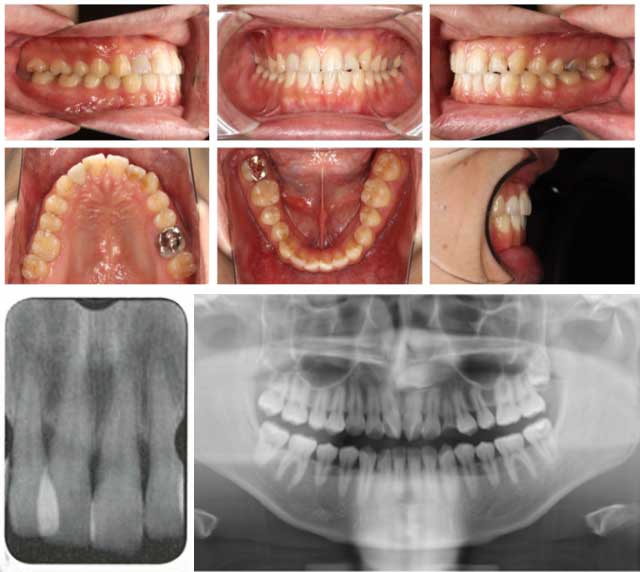

精密検査

口腔内診査、写真検査、模型検査、X線検査等で現状を詳細に確認します。

STEP

2